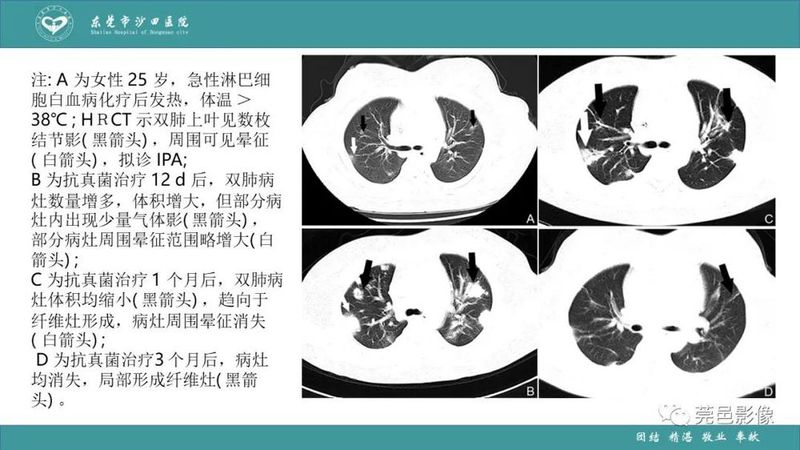

「肺炎克雷伯杆菌肺炎」影像学诊断+鉴别诊断